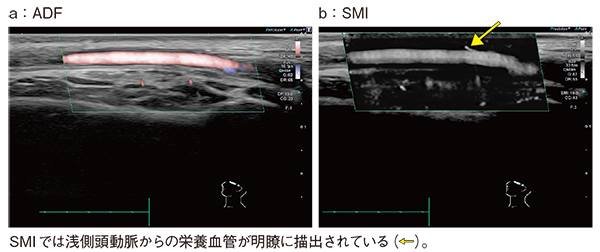

SMIは,全身のさまざまな領域に用いられており,造影剤を使用することなくプラーク内新生血管内の微細な血流評価も可能である(図4)。これは,SMIが低流速な血流の評価に有用であることを示していると言える。

図4 SMIによるプラーク内新生血管の描出(脳梗塞の原因精査)

また,SMIでは血管の内腔面と壁との境界を明瞭に描出可能である。断層像やカラードプラはもとより,ADF(Advanced Dynamic Flow)でも描出が不十分であった頸動脈の潰瘍病変が,SMIでは明瞭に描出されている(図5)。

図5 SMIによる頸動脈潰瘍病変の描出能の向上

図6は大腿静脈で,ADF(a)でも逆流の有無は視認できるが,SMI(b)では逆流に加え,不全弁周囲に残存する遅い血流の特定も容易である。

図6 SMIによる不全弁周囲の低流速部位の特定